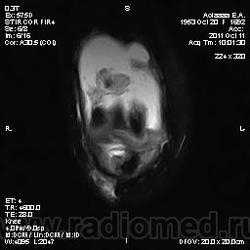

Дискуссия о природе "структры" в проекции передней поврехности метадиафиза бедренной кости.

Две версии: А. костно-хрящевой экзостоз. Б. разрастания сумки.

Я за экзостоз, но Вставьте снимки!))

МРТ изобрели зря.

Всё же не впечатляет масштаб.

Не очень понял. Мало картинок? Небольшой экзостоз? Неинтересный дифряд?

Они же не НЕ увеличиваются. Размер как на превьюшках: 256 x 256 тoчeк. Так и задумано?

Да, надо отметить, что "это" прекрасно видно на рентгенограммах. Вопрос к автору ветки - кто направил пациента на МРТ и с каким диагнозом?

Пациента на МРТ прислали с травмой. "Это" было выявлено в ряду другой патологии как случайная находка. Рентген не было возможности сделать - дистанционная диагностика. Хотя это конечно была первая мысль. Спасибо за внимание к посту.

Окончательное мнение - костно-хрящевой экзостоз. Прилагаю РКТ коленного сустава (пациент не тот, что на МРТ)

Валентин Львович, хочу обратить Ваше внимание, что это два разных кейса со сходной на мой взгляд патологией - костными экзостозами (другую временно опускаем) - взгляд со стороны МРТ и РКТ

За надколенником по передней поверхности бедренной кости на МРТ и РКТ (наверное не так наглядно) - костно-хрящевой экзостоз.

+ на РКТ проекционно на уровне средней трети диафиза бедренной кости кпереди от нее - фокусы хондроматоза.

tatyana, Вы в чем то правы. Складывается впечатление что кортикальная пластинка бедренной кости почти не изменена (или не изменена вовсе). Поэтому и были сомнения. Кроме того можно отметить, что вся синовиальная оболочка бурсы тотально утолщена, что тоже наводила на определенные соменения. Наверное изменение кортикальной пластинки, которые абсолютно четко увяжут заключение с костно-хрящевым экзостозом, можно указать с "натяжкой". Скорее это волевое решение в пользу костно-хрящевого экзостоза. Еще были мнения "вилонодулярном синовиите", а также "хондроматозе". Так что возможны варианты.